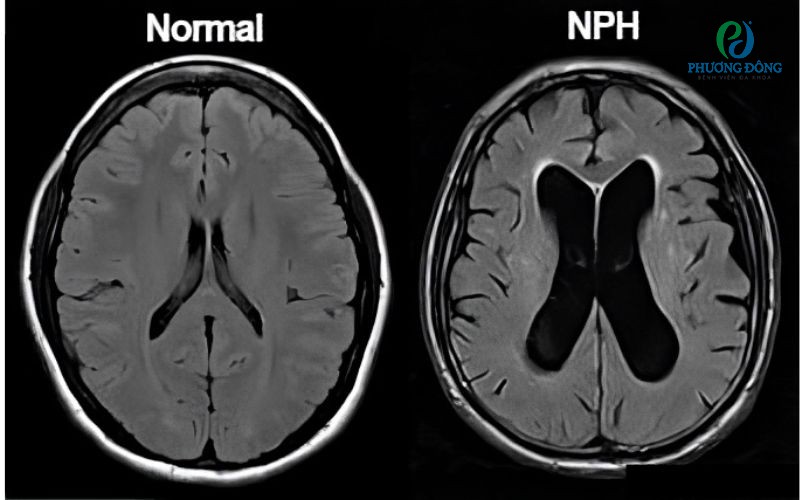

Chẩn đoán chủ yếu dựa trên sự kết hợp giữa triệu chứng lâm sàng và hình ảnh học. Chụp cộng hưởng từ sọ não MRI thường cho thấy hình ảnh não thất giãn rộng, đôi khi kèm theo một số dấu hiệu đặc trưng khác.